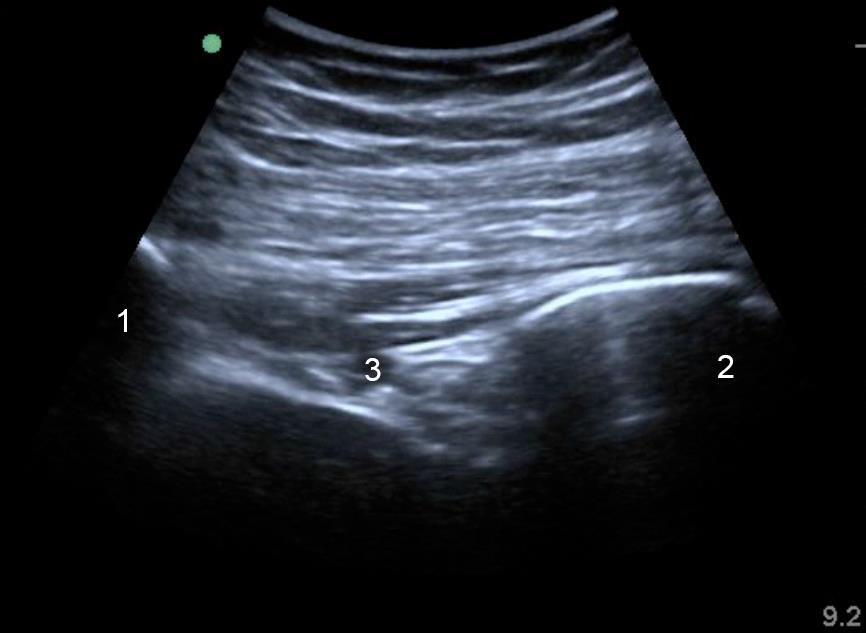

Imagen 3 de la estructura ósea de la parte posterior de la cadera

1. Sacro

2. Isquion

3. Arteria glútea inferior